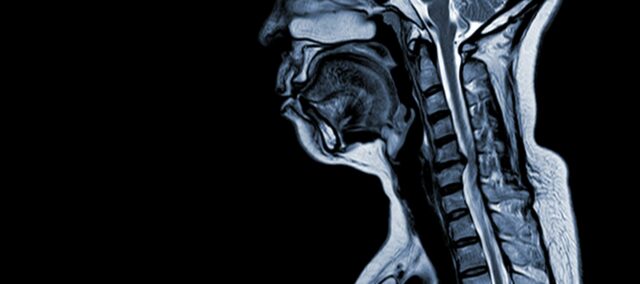

Шейная спондилотическая миелопатия (ШСМ) - это неврологическое заболевание, которое является основной причиной травм спинного мозга у взрослых. Проще говоря, речь идет о сдавливании или повреждении спинного мозга в шее, в первую очередь из-за естественного процесса старения, который затрагивает шейные позвонки. Термин "миелопатия" происходит от греческих слов "myelon", что означает "спинной мозг", и "pathos", означающего "болезнь".

CSM - сложное медицинское состояние с многофакторной патофизиологией, включающей структурные изменения в шейном отделе позвоночника. Несколько ключевых факторов способствуют его развитию и прогрессированию:

- Дегенерация диска (выпуклый диск): CSM часто начинается с дегенерации межпозвоночных дисков в шейном отделе позвоночника, из-за чего они выбухают или выпячиваются в спинномозговой канал.

- Субпериостальное костное образование (вентральнее спинномозгового канала): В ответ на повышенную механическую нагрузку организм образует новую костную ткань на передней (вентральной) стороне позвоночного канала, потенциально сужая пространство для спинного мозга.

- Окостенение задней продольной связки: Задняя продольная связка может подвергаться окостенению, затвердевать и кальцифицироваться, способствуя сужению позвоночного канала.

- Гипертрофия связочного аппарата (Ligamentum Flavum): Гипертрофия Ligamentum Flavum приводит к тому, что она утолщается и становится менее гибкой, еще больше ущемляя пространство внутри позвоночного канала и сдавливая спинной мозг.

Эти структурные изменения в совокупности приводят к компрессии и сужению позвоночного канала, что приводит к появлению характерных симптомов и осложнений, связанных с CSM. Распознавание этих факторов риска и понимание задействованных патофизиологических механизмов крайне важно как для профилактики, так и для лечения. Ранняя диагностика и соответствующие меры крайне важны для смягчения последствий этих структурных изменений в спинном мозге.